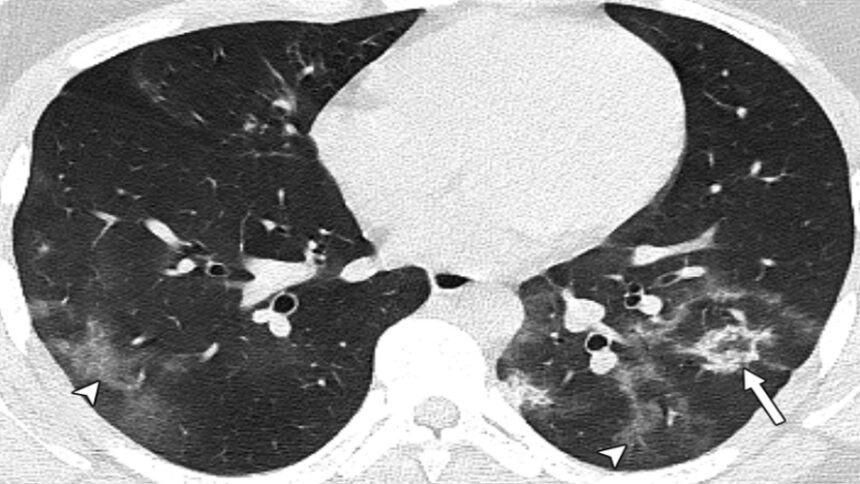

Μια εικόνα-χίλιες λέξεις στην οποία φαίνονται οι βλάβες που έχει προκαλέσει ο κοροναϊός στους πνεύμονες ανήλικων ασθενών οι οποίοι ΔΕΝ είχαν υποκείμενα νοσήματα ανήρτησε στον προσωπικό του λογαριασμό στο Facebook ο επίκουρος καθηγητής στο Τμήμα Υγιεινής και Επιδημιολογίας της Ιατρικής Σχολής του ΕΚΠΑ και μέλος της επιτροπής των εμπειρογνωμόνων, Γκίκας Μαγιορκίνης.

«Μία εικόνα χίλιες λέξεις. Αξονικές τομογραφίες νέων κάτω από 18 έτη με Covid-19 (18 ετών, 15 ετών, 14 ετών και 8 ετών). Κανένας ασθενής δεν είχε υποκείμενα νοσήματα ή ανοσοκαταστολή. Οι ασθενείς δεν χρειάστηκαν συμπληρωματικό οξυγόνο, διασωλήνωση ή ΜΕΘ. Πρόκειται για απλά-κοινά περιστατικά Covid-19. Ωστόσο έχουν πολύ «εντυπωσιακές» βλάβες και είναι άγνωστο τι θα προκαλέσουν αυτές οι βλάβες σε βάθος χρόνου. Για την πλειονότητα του κόσμου το ερώτημα είναι απλό: Θέλουν να υποβάλουν τους πνεύμονές τους σε αυτές τις βλάβες για να δουν αν αντέχουν; Και αν αντέξουν την πρόκληση (όπως προβλέπεται ότι θα αντέξουν οι περισσότεροι νέοι) θέλουν να δουν πόσα χρόνια ή αντοχές έχασαν στην πορεία; Με το εμβόλιο προστατεύουμε τους πνεύμονές μας από βαρύτατη καταπόνηση».